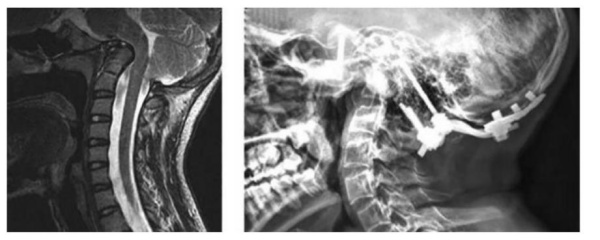

❖ Cột sống: Đốt sống thường loãng và hay bị xẹp, lỏng các phức hợp dây chằng dẫn đến các biến dạng như vẹo, gù. Vẹo cột sống gặp khoảng 20 – 40% bệnh nhân, thường gặp đoạn cột sống ngực Một số bệnh nhân sẽ có trượt đốt sống tiến triển. Cột sống cổ có thể gãy hoặc mất vững nhưng hiếm, nhưng nếu biểu hiện có thể gây biến dạng cột sống cổ, chèn ép hạnh nhân tiểu não, thiếu sót thần kinh.

- Chụp MRI nếu nghi nghờ chèn ép nền sọ.

❖ Điều trị chèn ép nền sọ [5]

- Chỉ định khi lâm sàng có triệu chứng, tổn thương rõ trên phim MRI cột sống cổ.

- Phương pháp: Thường giải ép và nẹp cổ chẩm (Đường sau)